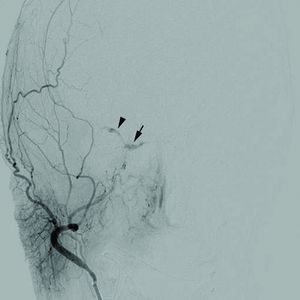

Cerebral angiogram of a carotid-cavernous fistula